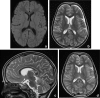

Background and purpose: The splenium of the corpus callosum is the most posterior part of the corpus callosum. Its embryological development, anatomy, vascularization, function, imaging of pathology, possible pathophysiological mechanisms by which pathology may develop and the clinical consequences are discussed.

Methods: A literature-based description is provided on development, anatomy and function. MR and CT images are used to demonstrate pathology. The majority of pathology, known to affect the splenium, and the clinical effects are described in three subsections: (A) limited to the splenium, with elaboration on pathophysiology of reversible splenial lesions, (B) pathology in the cerebral white matter extending into or deriving from the splenium, with special emphasis on tumors, and (C) splenial involvement in generalized conditions affecting the entire brain, with a hypothesis for pathophysiological mechanisms for the different diseases.

Results: The development of the splenium is preceded by the formation of the hippocampal commissure. It is bordered by the falx and the tentorium and is perfused by the anterior and posterior circulation. It contains different caliber axonal fibers and the most compact area of callosal glial cells. These findings may explain the affinity of specific forms of pathology for this region. The fibers interconnect the temporal and occipital regions of both hemispheres reciprocally and are important in language, visuospatial information transfer and behavior. Acquired pathology may lead to changes in consciousness.